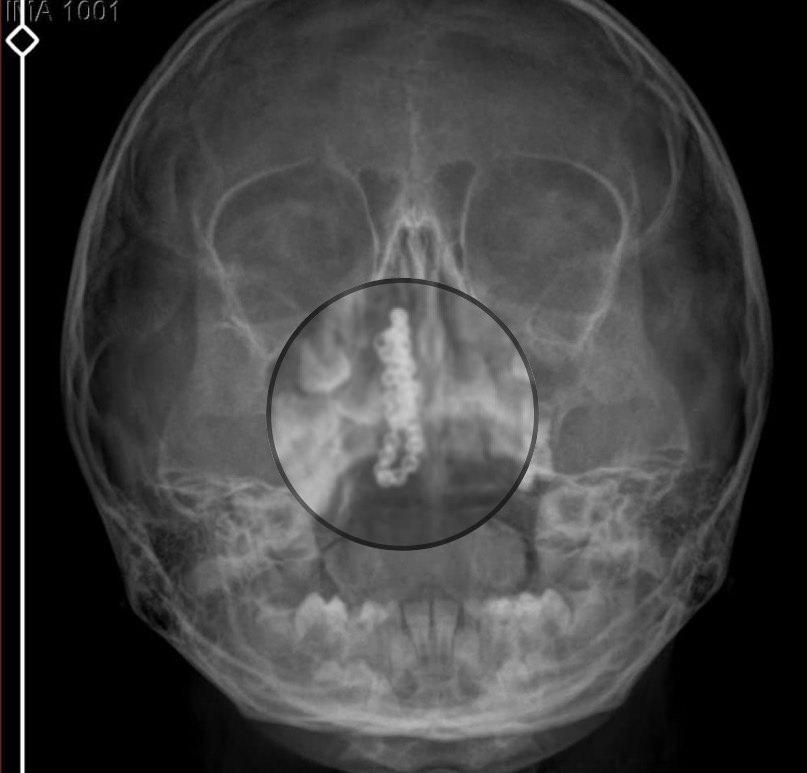

Devlet hastanesindeki doktorun incelemesi ve kapsamlı röntgen çekilmesi sonrası Polen'in burnunda metal cisim olduğu fark edildi.

2 yıldır burunda kaldığı değerlendirilip, küçük top şeklinde tırnak makası zinciri olduğu belirlenen cisim, başarılı ameliyatla çıkarıldı.

Kızının burnundan sürekli siyah renkte akıntı olduğunu anlatan Gökhan Tekin, "Çocuğumun burnundan kanama ile sürekli siyah akıntı geliyordu. Özel hastaneye götürdüm. Özel hastanede film çekildi, hiçbir bulguya rastlanılmadığı söylendi. O siyah leke de enfeksiyona dayalı olan bir şey olduğu bize söylendi. Eve geldik, akıntı sürmesi üzerine bu kez devlet hastanesine başvurduk. Burunda metal zinciri fark ettiler. Böyle bir ihmalkarlık olabilir mi? Özel hastaneye gidiyoruz, paramızla rezil oluyoruz. Zincir, 2 yıldır burnunda ve devletimizin hastanesinde iyi bir doktorumuz zinciri ortaya çıkarıyor, kızım ölümden dönüyor. Ben sonuna kadar bu işin peşini bırakmayacağım. Sonuna kadar hukuk mücadelesi vereceğim. Bu da diğer hastalarımıza ibret olsun. İşte, bakın koca bir zincir. 'Bulguya rastlanılmadı' deniliyor" dedi.

Kızının ameliyat sonrası durumunun iyi olduğunu söyleyen Tekin, "İnanır mısınız bize 'Evde soba mı yanıyor? Acaba kömür isten dolayı mıdır bu?' dendi. Böyle bir şey olabilir mi? Ameliyattan çıkan parmağım kadar zincir. Devlet hastanesindeki doktor da 'Bu nasıl gözden kaçılabilir? Böyle bir pozisyon nasıl görülmeyebilir?' yorumunda bulundu. Allah'a şükür olsun atlattık. Şu anda durumu, vaziyeti iyidir. Ben şuna inanıyorum doktor da bir şans işidir. Bakın paramızla özele gideriz ya hani bizde, daha iyi ilgilenirler. Oysa devlet hastanesindeki doktorumuz olayı meydana çıkardı." diye konuştu.